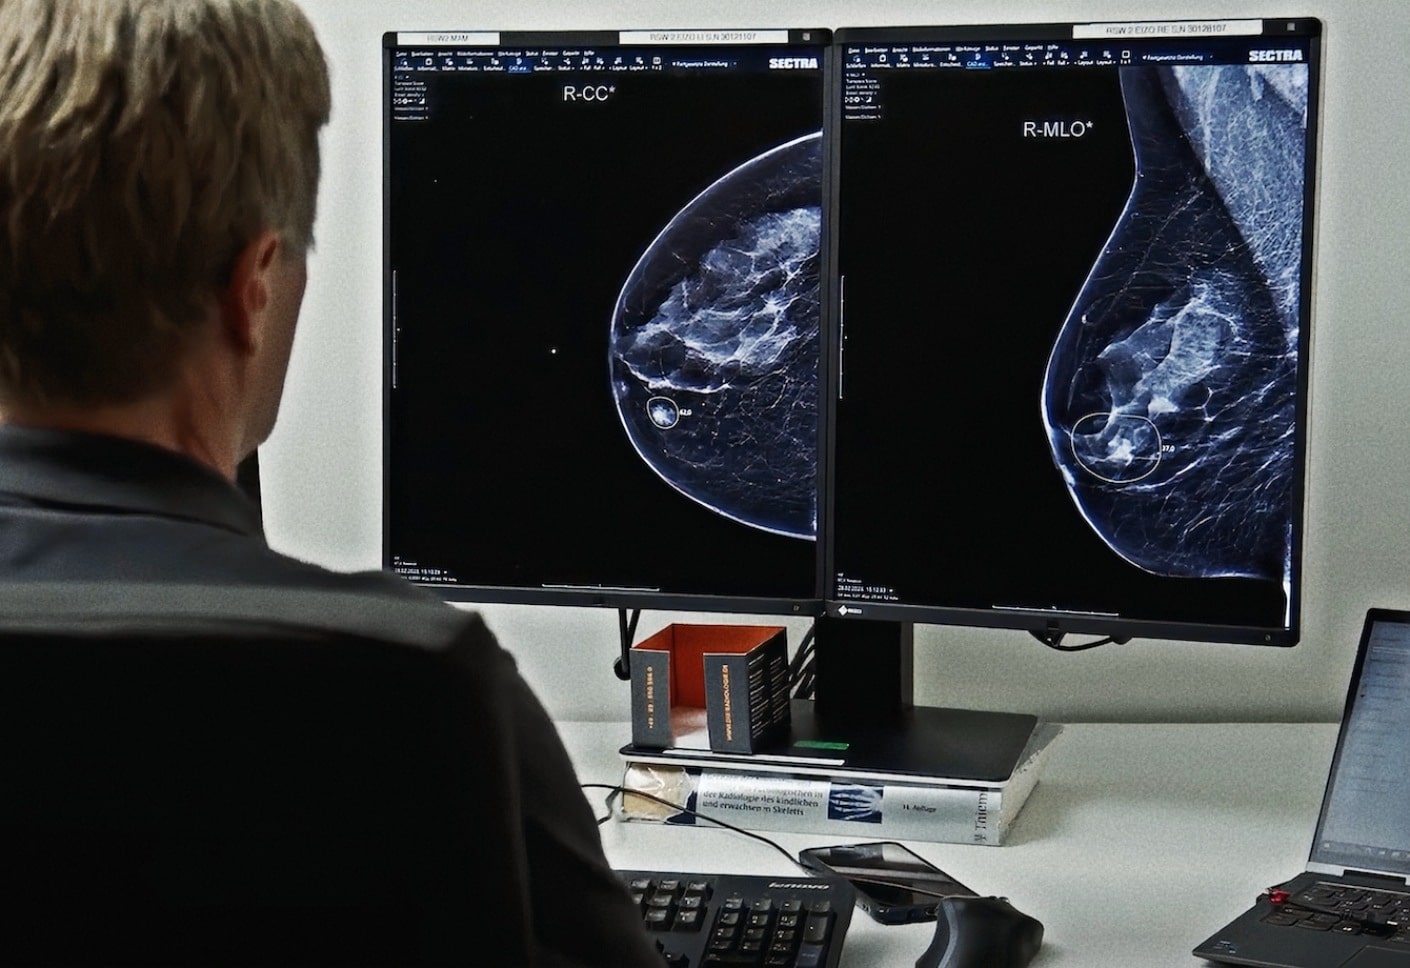

Lunit INSIGHT MMG (2D) mammography software supports earlier breast cancer detection, especially in dense breasts and interval cancers.

Designed for streamlined PACS and viewer integration, it delivers AI-driven insights during image review. This shortens reading time, supports single- and double-reading workflows, and helps address the shortage of breast imaging specialists in high-volume settings.

In a JAMA Oncology study, it outperformed other AI solutions with the highest accuracy and optimal sensitivity–specificity in detecting malignant lesions¹.

In a retrospective analysis, Lunit INSIGHT MMG correctly identified suspicious findings in a mammogram from 2020 that was originally overlooked. The patient was not diagnosed until 2022—highlighting the potential of AI mammogram reading tools to support earlier diagnosis.